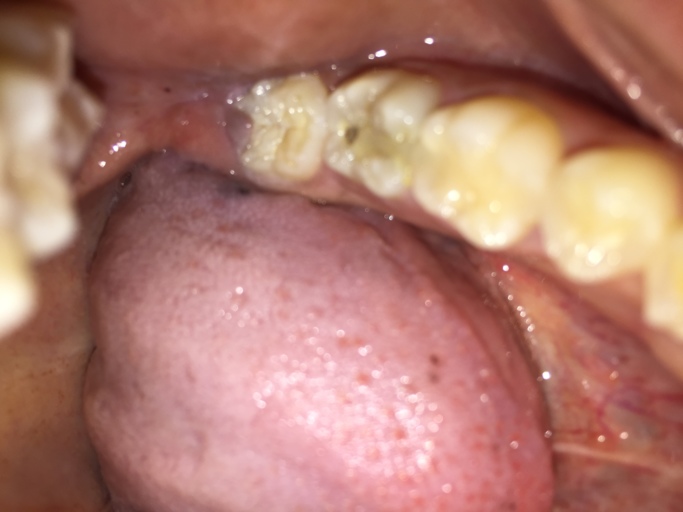

I just had a temporary filling on 7th September 2016 on my upper right premolar (decay started between my premolars). On 24th September, I returned for a permanent filling. Before he filled a permanent filling for my tooth he asked me whether I had any pain. I said no. So he filled my tooth with a permanent filling. He told me my filling is deep. After 1 month , 30th October, I felt pain when I chew on hard food only. Why? Should I avoid using that tooth? And also last week the tooth starts to feel sensitive when I rinse my mouth with cold tap water. What is happening? Do I need to x-ray my teeth?

You should not feel pain after a filling for a prolonged period of time.  It is normal for a tooth to be sensitive when the filling is large and sometimes it takes several weeks to subside.  It may be possible that by the time the decay was removed, it had already insulted the nerve of the tooth and now the nerve is dying.  With the temporary filling in place, more than likely it was medicated and soothing to the nerve, now with the permanent filling, the nerve is starting to die, causing discomfort.  You may need a root canal and a crown on this tooth.  Call your dentist and have an xray taken to see if there is pathology.  He/she can also test the response to cold, percussion and palpation to help in diagnosis and treatment in the future.